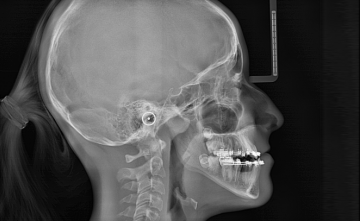

X-Mind Prime 3D теперь доступен в совершенно новой версии с цефалометрическим кронштейном, что расширяет области применения устройства до ортодонтии. X-MIND PRIME предназначен для использования в любой стоматологической сфере благодаря своему минималистичному и компактному дизайну, который в сочетании с непревзойденная простота в эксплуатации обеспечивает оператору и пациенту наилучшие впечатления от обследования.

СТИЛЬНЫЙ И ЭФФЕКТИВНЫЙ

X-Mind® prime 3D Ceph сочетает в себе минималистичный и компактный дизайн с исключительной простотой использования. Новый цефалостат, специально разработанный для обеспечения максимального комфорта и стабильности пациента, и встроенная в ушной стержень интеллектуальная опорная плоскость Франкфурта, всегда обеспечивают быстрое и точное позиционирование пациента.

ПРЕВОСХОДНОЕ КАЧЕСТВО ИЗОБРАЖЕНИЯ

Использование современного цифрового датчика в сочетании с высокой производительностью программного обеспечения Acteon Imaging Suite обеспечивает превосходное качество изображения и непревзойденную надёжность при цефалометрии.

БЫСТРОЕ И ТОЧНОЕ СКАНИРОВАНИЕ ЦЕФАЛОМЕТРИИ

Выбор до 17 различных цефалометрических программ, включая высокоскоростное сканирование (всего 4,4 с) и новые режимы уменьшенного размера для обеспечения идеальной оценки интересующей области при минимальной дозе облучения.